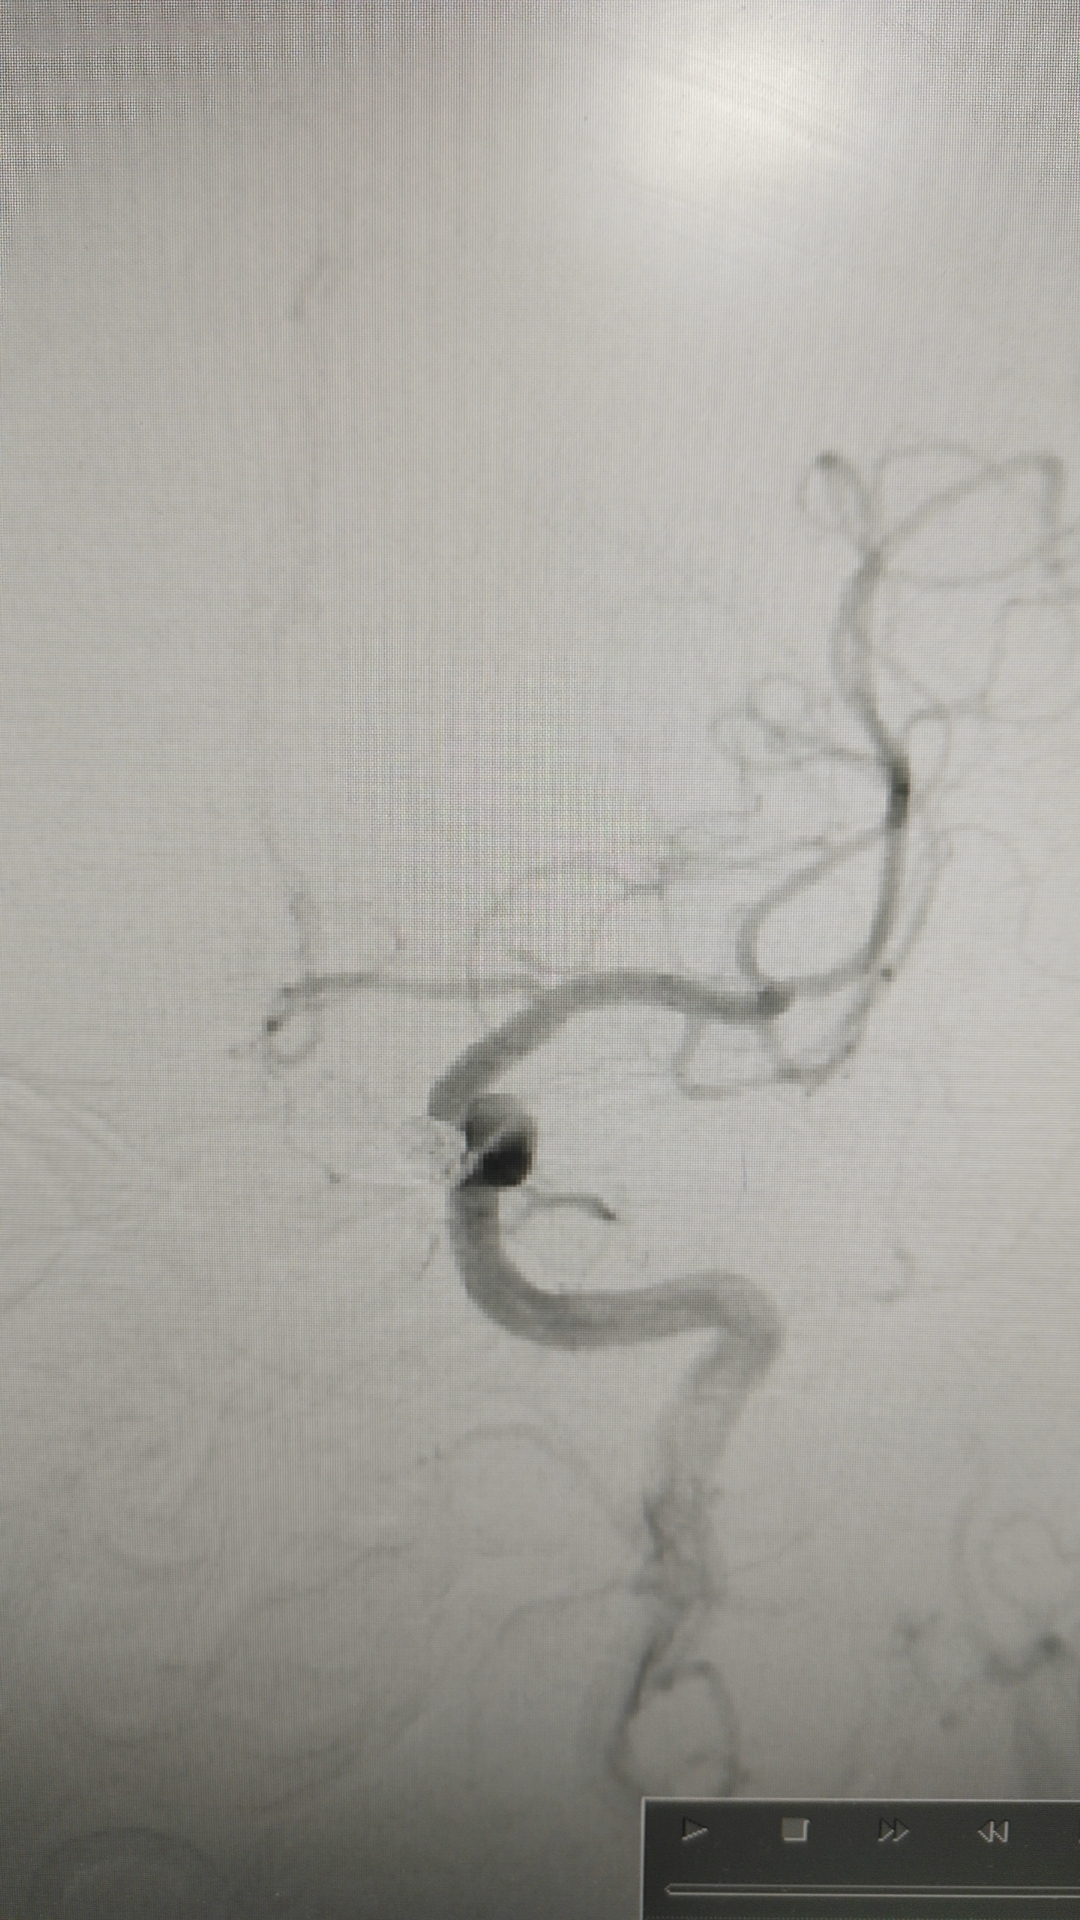

当地医院手术时造影,左侧颈内动脉眼动脉段动脉瘤

栓塞后

当地医院造影右侧颈内动脉床突上段瘤样突起,约1mm,未处理!